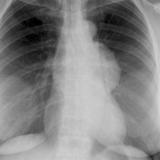

Case 8a Thymoma PA

Date: 03/27/2009

Views: 9450